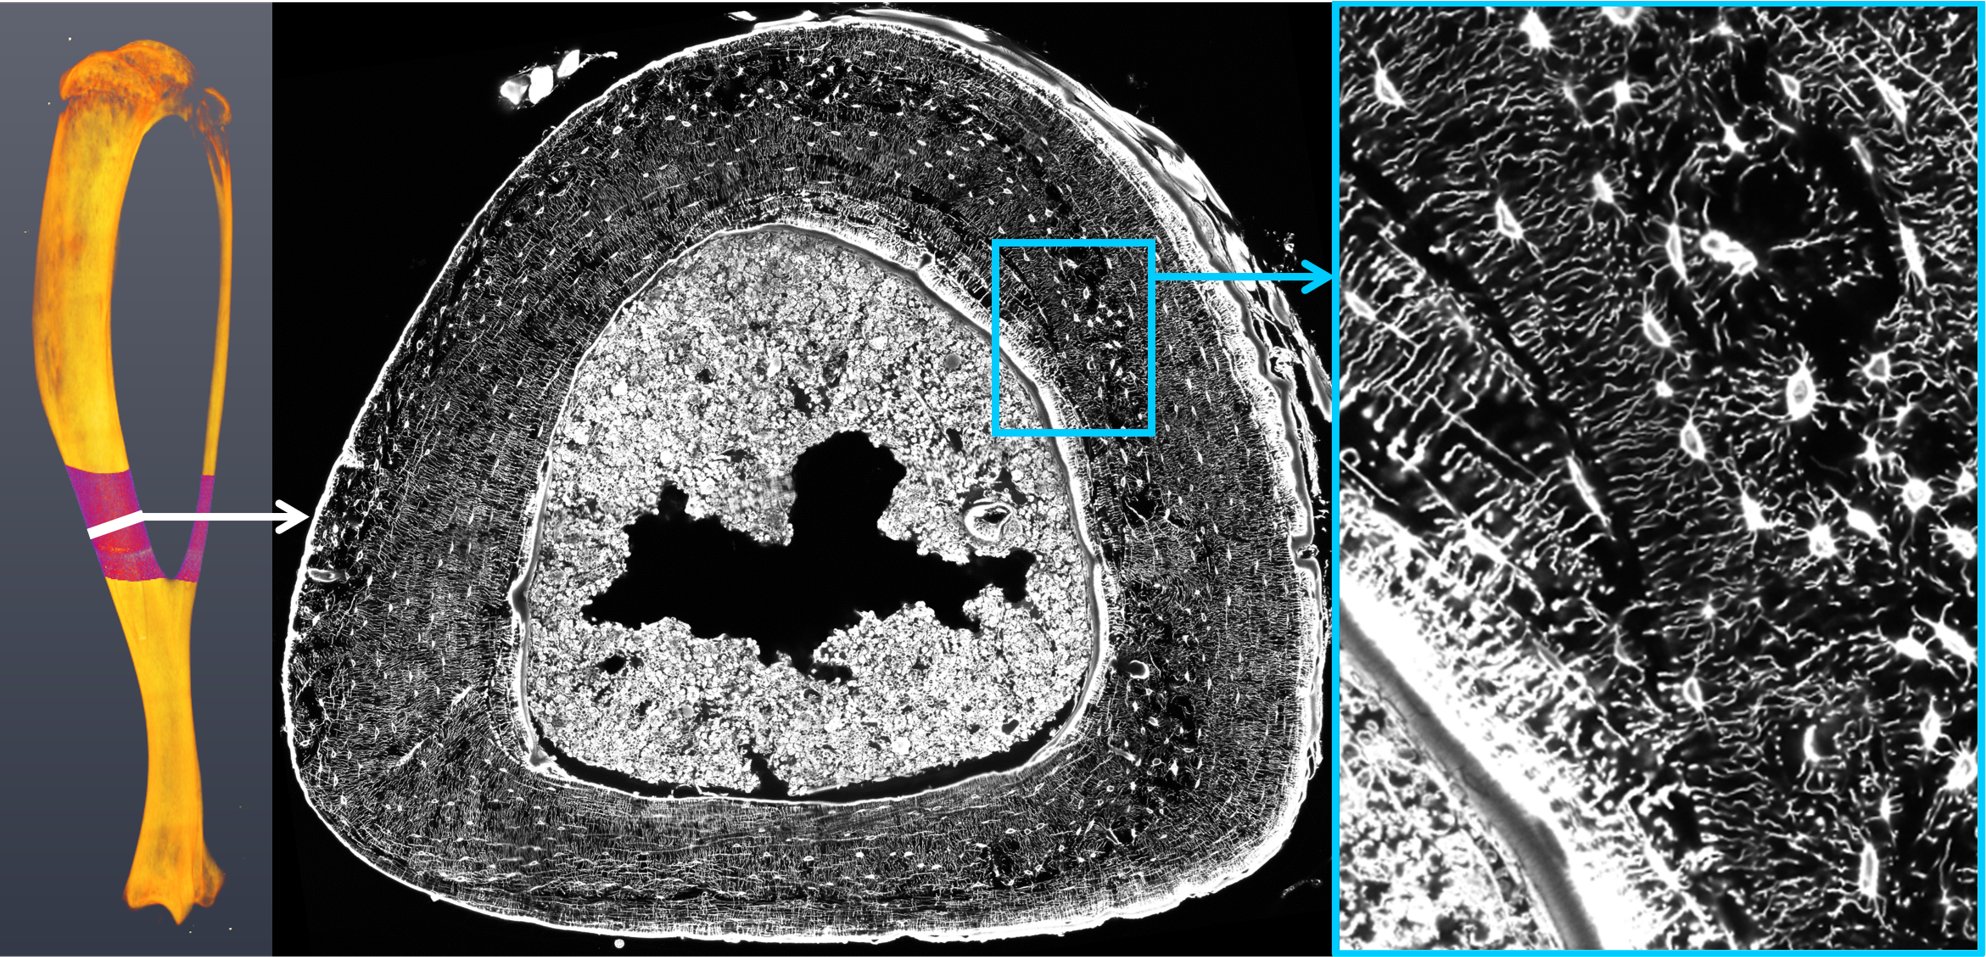

Kooperationsstudie zum Zellnetzwerk der Knochen in renommierter Zeitschrift „Proceedings of the National Academy of Science of the USA“ veröffentlicht

Knochen haben die außergewöhnliche Eigenschaft sich an äußere mechanische Einflüsse anzupassen und gezielt dort neues Material aufzubauen, wo es am dringendsten benötigt wird. Bereiche, die nur schwachen mechanischen Belastungen ausgesetzt sind, werden hingegen abgebaut.